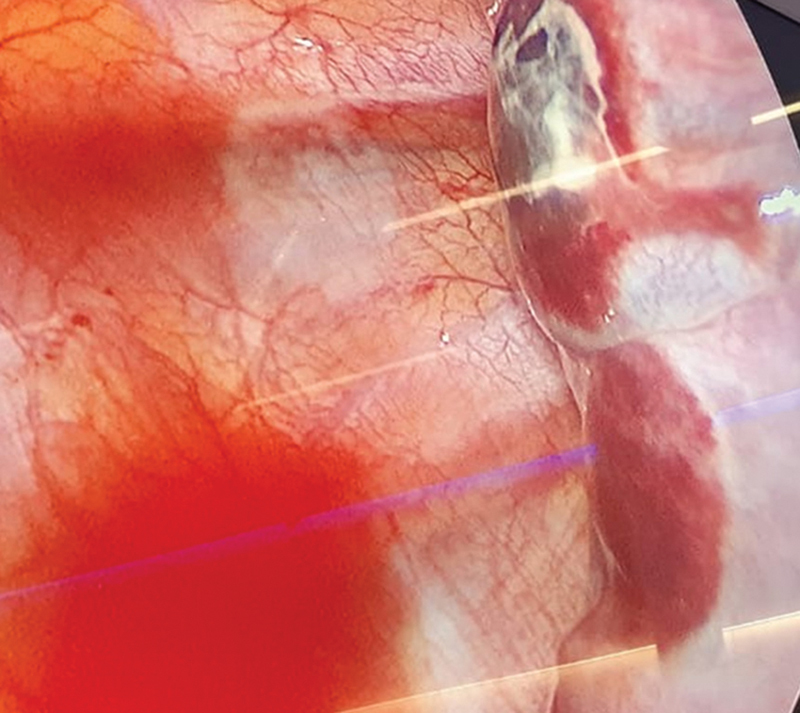

A 13-year-old male patient with marfanoid features and pectus excavatum with Haller index 4 and correction index of 38% underwent the Nuss procedure with cryoanalgesia 9 days prior, which transpired uneventfully. Preoperative spirometry was normal, and echocardiogram showed light aortic valve dilation. A month later, during a routine outpatient checkup, he referred middle abdominal pain, denying respiratory symptoms nor thoracic pain. He presented bilateral apical and right basal hypophonesis. Chest X-ray revealed bilateral pneumothorax and right pleural effusion. Consequently, the patient was admitted to the emergency room, and a chest computed tomography was ordered, reporting right apical blebs. Bilateral thoracoscopy was performed, and apexes were checked for pulmonary blebs to rule out primary pneumothorax. In the right chest, a wedge resection of a distorted area on the apex and pleuroabrasion were done. Four air leaking eschars were found when performing lung expansion under water as leaking test, corresponding to cryoanalgesia intercostal eschars, and subsequently closed by primary suture. In the left chest, there were no blebs. However, another four pleural lesions with intact pleura in the left lower lobe were also found. Postoperative course was uneventful and chest drains were removed 48 hours after surgery. He remains asymptomatic 21 months after discharge. Cryoanalgesia in pectus excavatum is spreading due to the improvement in postoperative pain control. However, some complications may occur.

Abstract Image